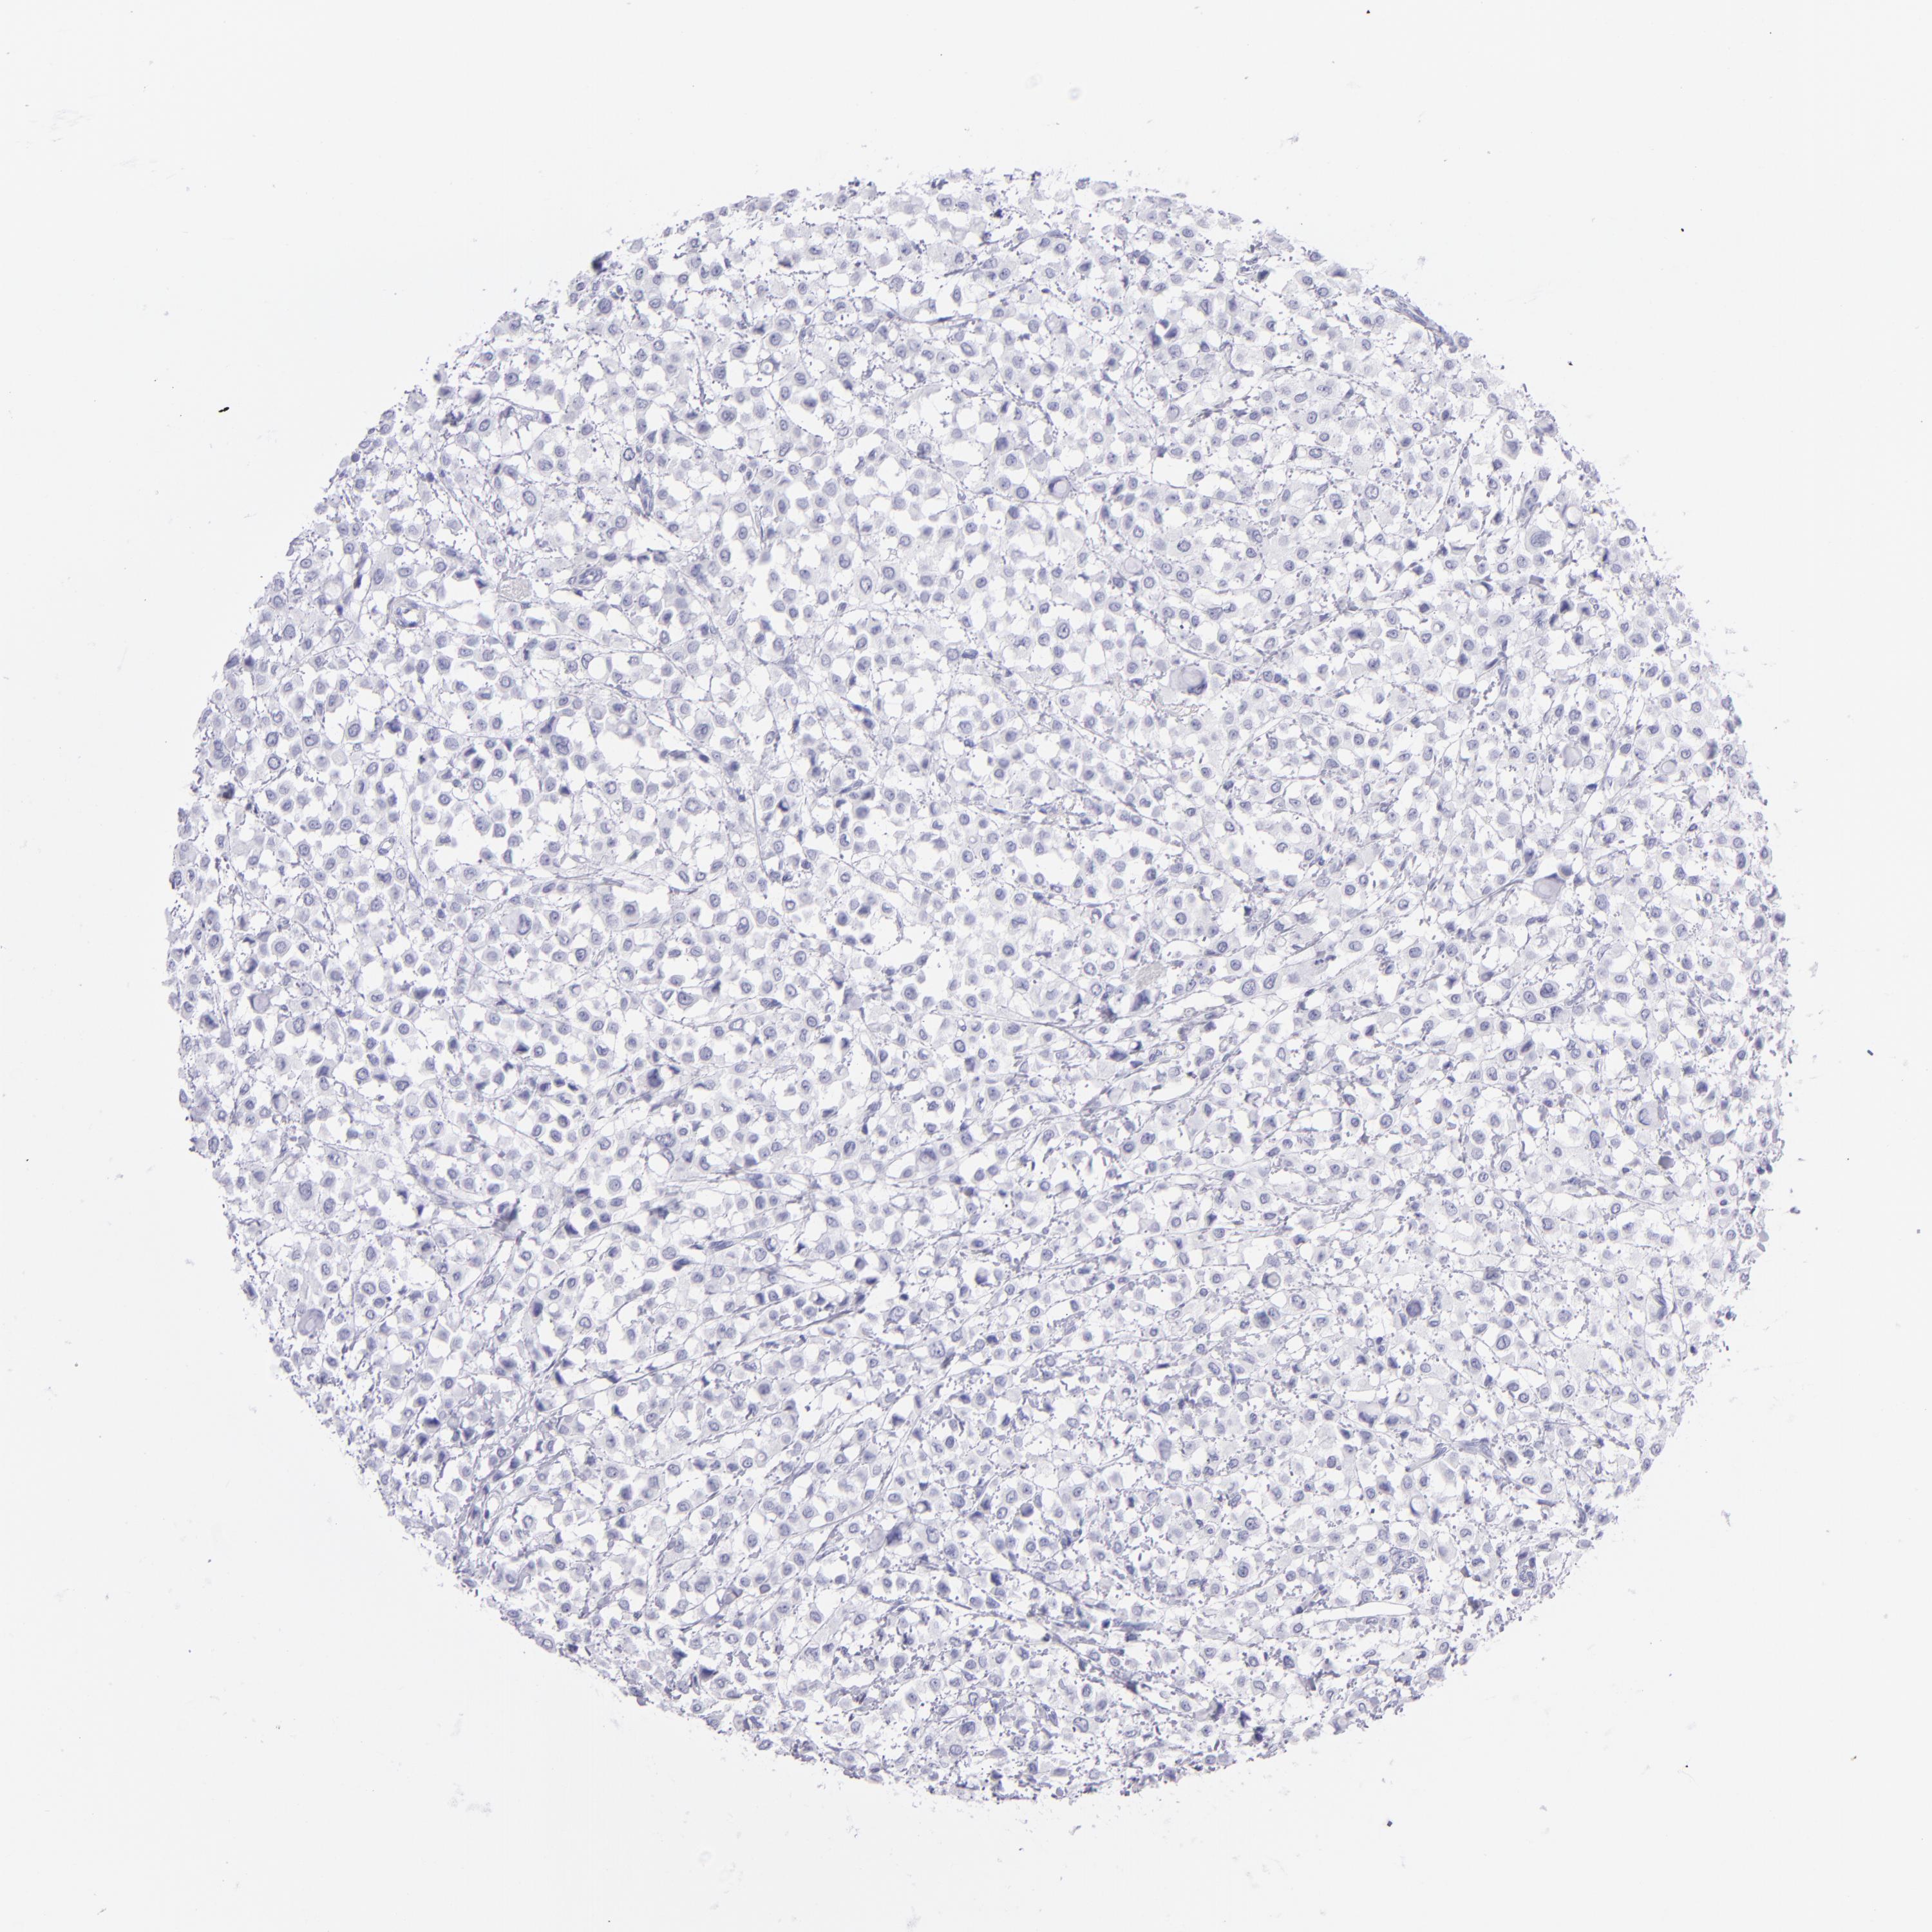

BRCA TCGA BRCA VALIDATION PROTEIN EXPRESSION

ANTIBODIES

AND

VALIDATION